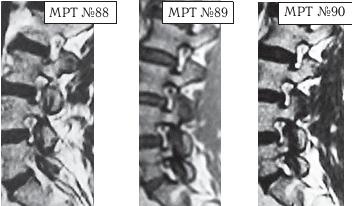

На МРТ № 88 наблюдается состояние до лечения методом мануальной терапии: дегенеративно-дистрофический процесс во всех межпозвонковых дисках поясничного отдела позвоночника, спондилёз, остеофитоз, спондилоартроз дугоотростчатых суставов в сегментах LIII-LIV, LIV-LV, LV-SI а также стеноз фораминальных отверстий в данных сегментах.

На МРТ № 89 наблюдается состояние того же пациента сразу после проведения лечебного сеанса мануальной терапии (в течение одного часа).

Объективно положительных изменений при визуальном сравнении МРТ-снимков до и после проведения лечебного сеанса мануальной терапии не наблюдается. Стеноз фораминальных отверстий без изменений, соотношения суставных поверхностей дугоотростчатых суставов — без изменений.

Объективно отрицательные изменения при визуальном сравнении МРТ снимков до и после проведения лечебного сеанса мануальной терапии наблюдаются и проявляются кровоизлиянием в полость дугоотростчатых суставов в сегментах LIII-LIV, LIV-LV, LV-SI

На МРТ № 90 наблюдается состояние того же пациента после проведения трёх лечебных сеансов мануальной терапии с 24-часовым интервалом между сеансами.

Объективно положительных изменений при визуальном сравнении МРТ-снимков до и после проведения трёх лечебных сеансов мануальной терапии не наблюдается.

Объективно отрицательные изменения при визуальном сравнении МРТ-снимков до и после проведения трёх лечебных сеансов мануальной терапии наблюдаются и проявляются значительным кровоизлиянием в полость дугоотростчатых суставов в сегментах LIII-LIV, LIV-LV, LV-SI.

Для лучшего визуального сравнения приводятся соответствующие увеличенные фрагменты (МРТ № 91, МРТ № 92, МРТ № 93) снимков МРТ (МРТ № 88, МРТ № 89, МРТ № 90), на которых наблюдаются фораминальные отверстия и дугоотростчатые суставы сегментов LIII-LIV, LIV-LV, LV-SI.

Вывод: исходя из объективного визуального наблюдения, согласно снимкам МРТ-обследования и их сравнения, можно сделать вывод, что применение мануальной терапии в данном конкретном случае положительных изменений не дало. Кровоизлияние в полости дугоотростчатых суставов поясничного отдела позвоночника после применения мануальной терапии можно считать отрицательным результатом.